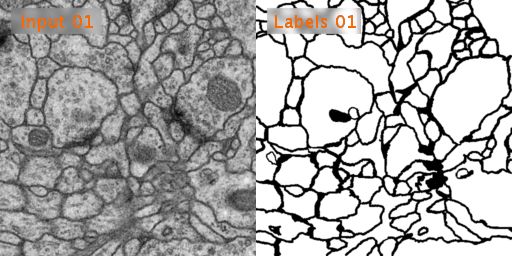

下面是输入的图像和标签:

我们来看看与其他方法相比,U-Net在EM图像分割方面的表现:

下面这是U-Net在PhC-U373 (a-b)和DIC-HeLa (c-d) 数据集上的分割,看起来还是比较成功的: